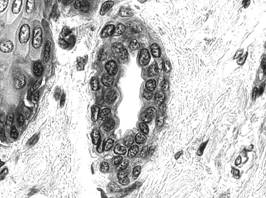

Fig. I.1.13. Epiteliu simplu cubic

- canalicul biliar (HE, x 400)

Fig. I.1.14. Epiteliu simplu cubic

- tubi contorti distali (HE, x 400)

In cadrul glandelor exocrine multe dintre canalele de excretie au un perete format din epiteliu simplu cubic - de exemplu, canalele biliare intrahepatice (fig. I.1.13), canalele din structura pancreasului exocrin si a glandelor salivare.

Cu toate ca nu sunt perfect cubice, ci au forma de trunchi de piramida, celulele epiteliului tubilor contorti renali (fig. I.1.14) pot fi incadrate in aceasta varietate.